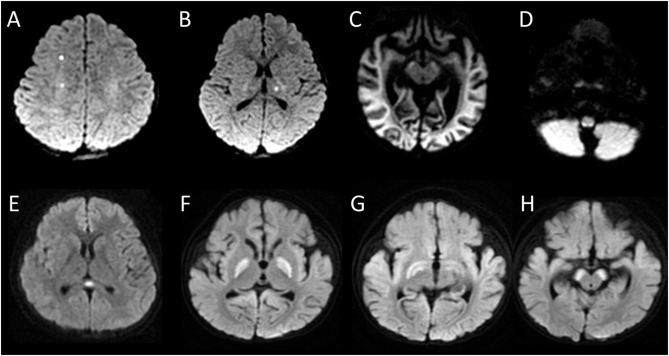

HIGH INCIDENCE of CEREBROVASCULAR LESIONS in CHILDREN during OMICRON outbreak 😨

Among 31 pediatric patients with post-COVID-19 neurological symptoms, MRI abnormalities were observed in 15 (48.4%), predominantly encephalitis/encephalopathy (73.3%). sciencedirect.com/science/articl…

2) It is the 2nd study published recently on patients who received MRI due to neurological symptoms after COVID-19 infection.

Here is the case of a 7-year-old girl with encephalitis and myoclonic status epilepticus Image